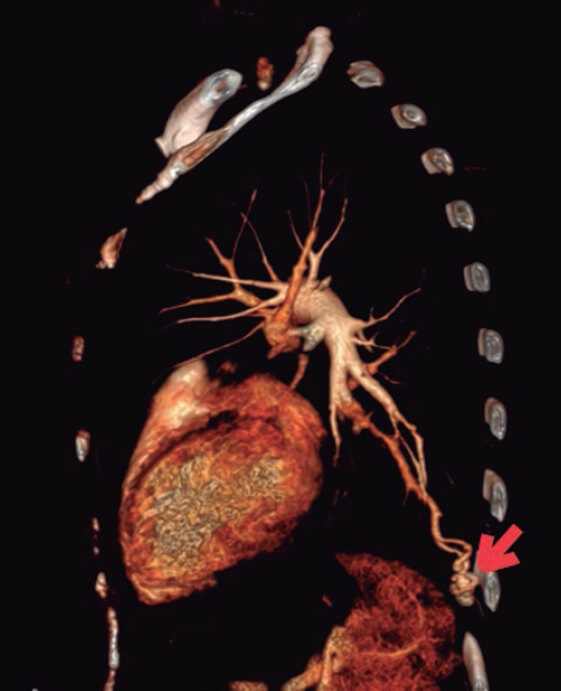

Para descartar un foco embolígeno se completó el estudio con ecografía Doppler de miembros inferiores, en la que no se observaron signos de trombosis venosa profunda. Dado el antecedente sindrómico de la paciente, se realizó una angiotomografía de tórax en busca de fístulas arteriovenosas pulmonares, y se confirmó la presencia de 2: una dependiente del territorio pulmonar izquierdo en el segmento posterobasal (figura 2, flecha) y otra, de menor tamaño, en el segmento laterobasal homolateral.

Figura 2.